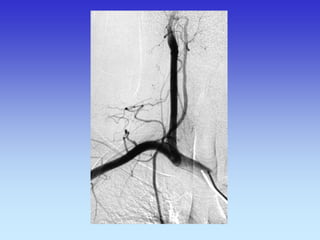

METODE PRIKAZA KRVNIH ŽILA

•UZ-DOPPLER

•DSA

•CTA

•MRA

B-mod i obojeni Doppler karotidne arterije